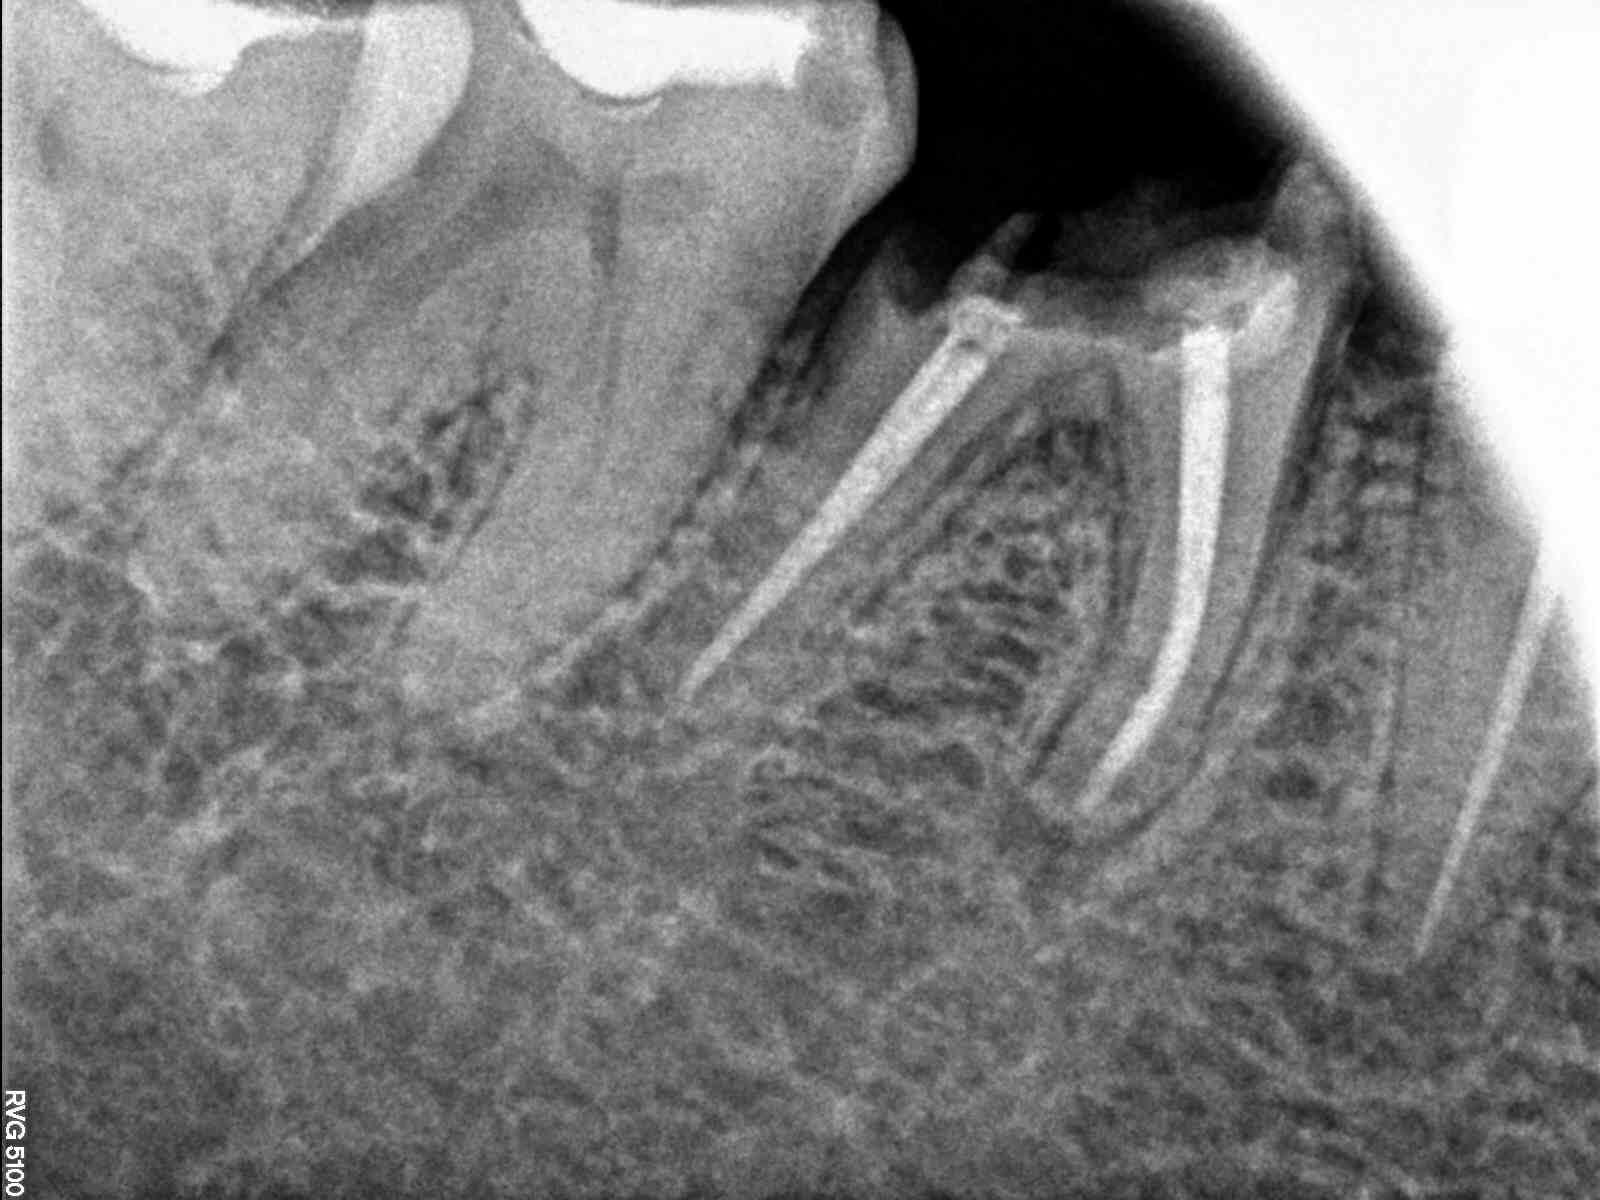

Extraction followed by immediate implant placement along grafting the Jump space. SCRP prosthesis was given finally. 1 Year follow up is also there.